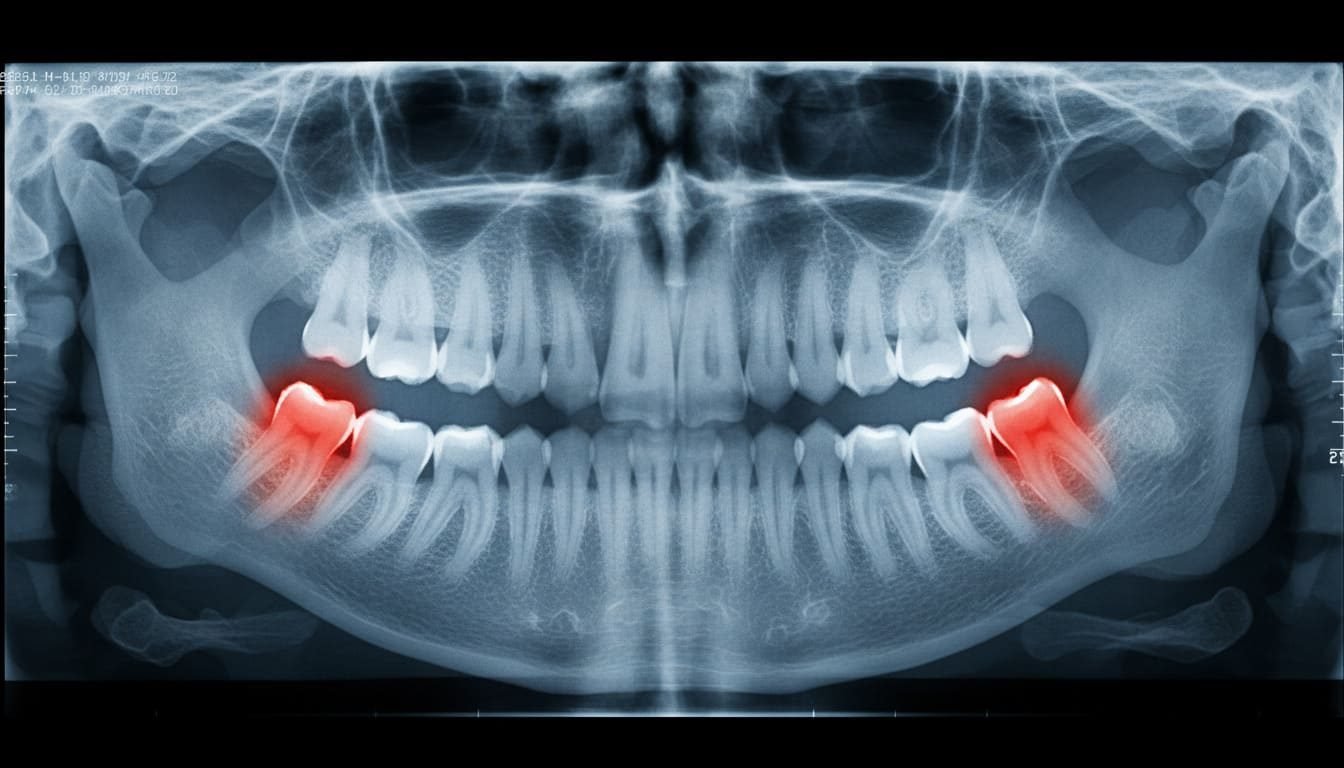

Основні ознаки

- Посилення легеневого малюнка. Можна порівняти з чорно-білим фетишем на фото.

- Тіньові зміни у верхніх ділянках легень. Як слід натякнути лікарю на цікавість до вашої любові до сигарет.

- Збільшення коріння. Не зовсім те, що ви могли побачити у глиняній мандрівці до бабусі.